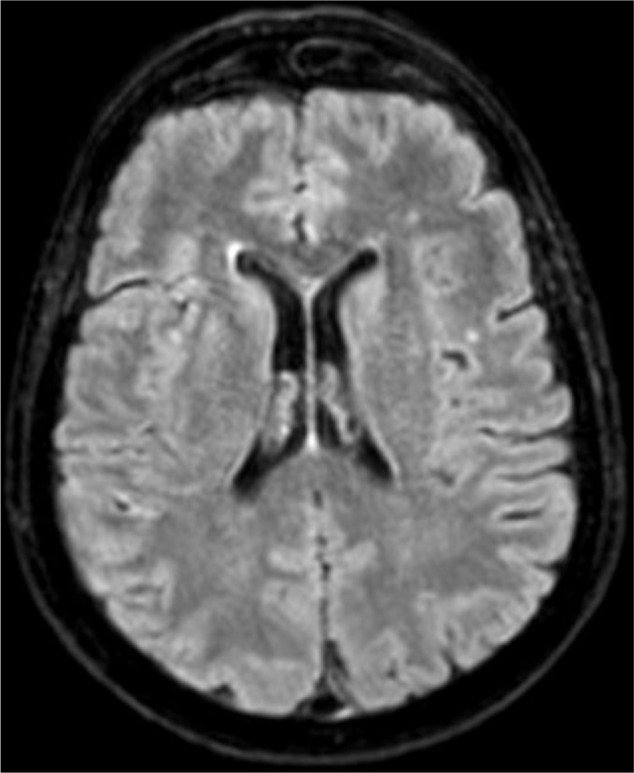

Questi pazienti presentano spesso atrofia corticale diffusa e infarti multipli della sostanza bianca subcorticale nei lobi frontali e temporali.

- MRI cerebrale: indispensabile per rilevare atrofia focale, lesioni del lobo frontale destro o alterazioni dei lobi temporali;

| Scala di Fazekas | Valutazione della malattia dei piccoli vasi (MRI). | Identifica danni vascolari che possono causare disconnessione. |